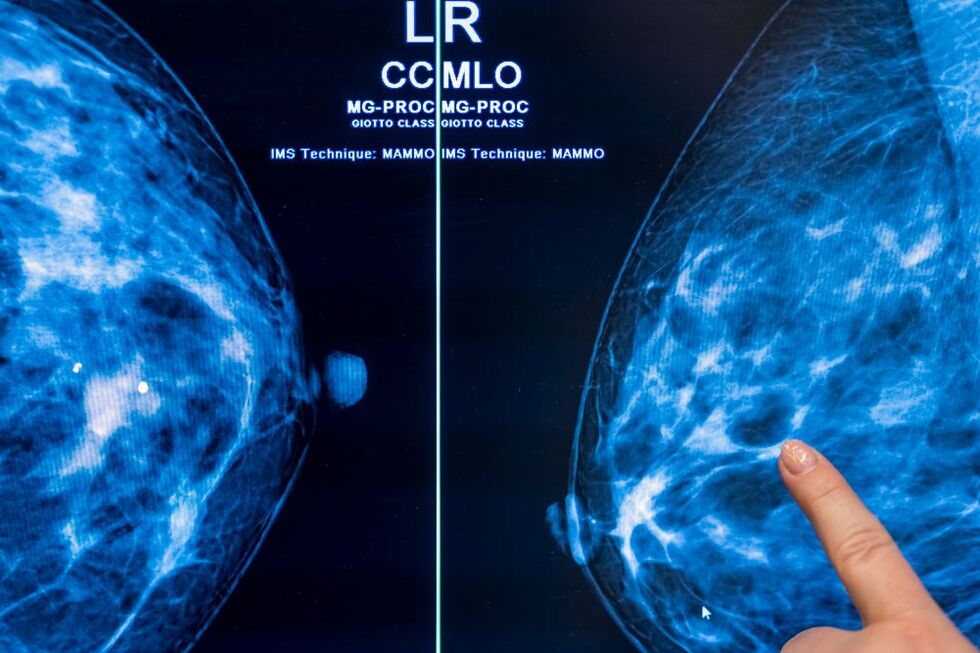

A percentagem de cirurgias oncológicas realizadas fora dos tempos máximos recomendados aumentou no primeiro semestre do ano, segundo a Entidade Reguladora da Saúde (ERS), que conclui que 22,4% dos utentes foram operados fora do prazo definido por lei.

Numa informação divulgada esta terça-feira relativa à monitorização dos tempos de espera no Serviço Nacional de Saúde (SNS) no primeiro semestre deste ano, a ERS diz que foram realizadas 34.439 cirurgias programadas na área de oncologia nos hospitais públicos (+12,2% face ao período homólogo).

O regulador refere um aumento da percentagem de incumprimento dos tempos de espera de cerca de 3,1 pontos percentuais, passando de 19,3% no primeiro semestre de 2023 para 22,4% este ano. Segundo a ERS, em 30 de junho, 7.127 utentes aguardavam cirurgia programada na área de oncologia, o que corresponde a um aumento de 1,1% face ao período homólogo, 16,7% dos quais com espera superior ao Tempo Máximo de Resposta Garantido (TMRG).